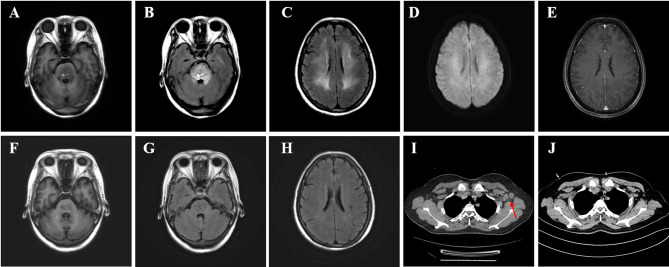

人培吉病毒(hpv)被认为是脑脊髓炎的潜在病因,并表现出嗜淋巴性特征。然而,脑炎和淋巴结病与hpv共发尚未见报道。在此,我们报告一例48岁的妇女入院发烧,随后突然失去意识。影像学表现为脑炎和淋巴结病。血液和脑脊液(CSF)的初步分析未能揭示具体的病因。在脑脊液中发现的唯一病原体后来通过宏基因组新一代测序(mNGS)确定为hpv。经阿昔洛韦、美罗培南和头孢曲松钠治疗后,患者完全康复。该病例为支持hpv致病潜力的假设提供了额外的证据,并突出了mNGS在检测罕见病原体方面的诊断效用。

Human pegivirus (HPgV) has been postulated as a potential etiological factor in encephalomyelitis and exhibits lymphotropic characteristics. However, the co-occurrence of encephalitis and lymphadenopathy with HPgV detected has never been reported. Herein, we report a case of a 48-year-old woman admitted with fever followed by sudden loss of consciousness. Radiological imaging demonstrated encephalitis and lymphadenopathy. Initial analysis of blood and cerebrospinal fluid (CSF) failed to reveal specific etiology. The only pathogen found in CSF was later determined to be HPgV using metagenomic next-generation sequencing (mNGS). After receiving treatment with acyclovir, meropenem, and ceftriaxone sodium, the patient fully recovered. This case contributes additional evidence in support of the hypothesis regarding the pathogenic potential of HPgV and highlights the diagnostic utility of mNGS in detecting rare pathogens.